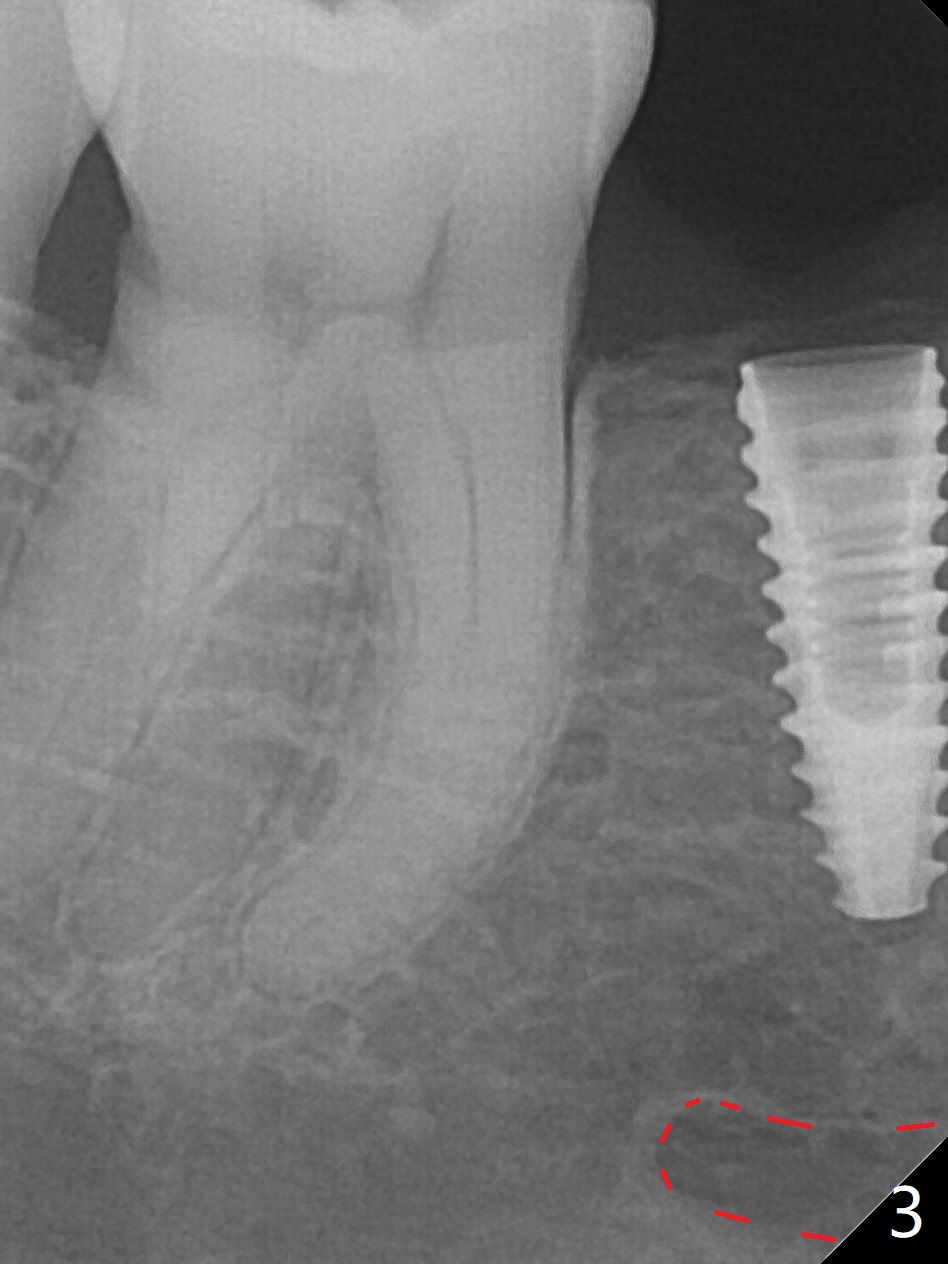

After incision the ridge at #29 is not so narrow as shown in Fig.1. But it is still intact, in contrast to what CBCT shows. Osteotomy is initiated with 1.2 mm drill, followed by 1/1.6, 1.3/2.3 and 1.7/3.1 mm DIO Bone Expanders. In fact mesial and distal crestal slots (BEB: bone expansion and bending) are created by using surgical fissure bur in order to insert the last bone expander in place (10 mm, Fig.2). Following 3.5 mm Cortical Tap, a 3.5x10 mm IS Implant is placed ~ 50 Ncm with clearance from the Mental Loop (Fig.3,4 red dashed line) and slightly subcrestal (Fig.5). The most distal part of the distal slot created for BEB is shown in Fig.5 *. Bone resorption is minimal 4 months postop (Fig.6,7). The implant was apparently placed in the middle buccolingually (Fig.8).